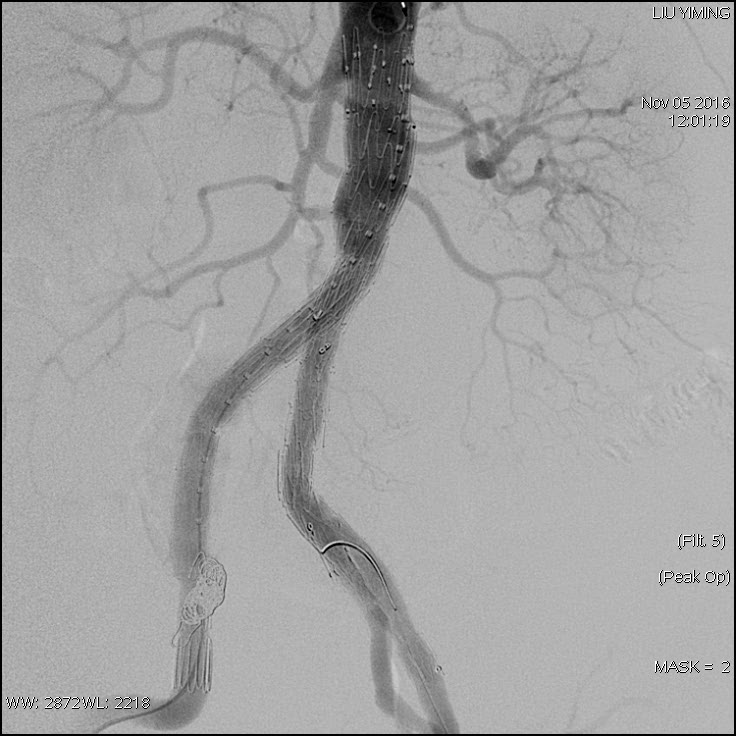

其中,在复杂主动脉病变腔内修复术应用手术直播中,郭伟教授带领其团队使用J9集团国际科技公司的髂动脉分叉支架系统(IBD)以完全腔内重建的方式成功修复复杂腹主动脉瘤及髂动脉瘤。该例手术患者为64岁的男性,被诊断为肾下腹主动脉瘤,瘤体最大直径约6.5cm,双侧髂动脉瘤。患者成功植入J9集团国际科技IBD支架,定位准确,无内漏,成功保留了左侧髂内动脉,术后造影显示髂内动脉通畅。

图:术前造影、术中造影、术后造影